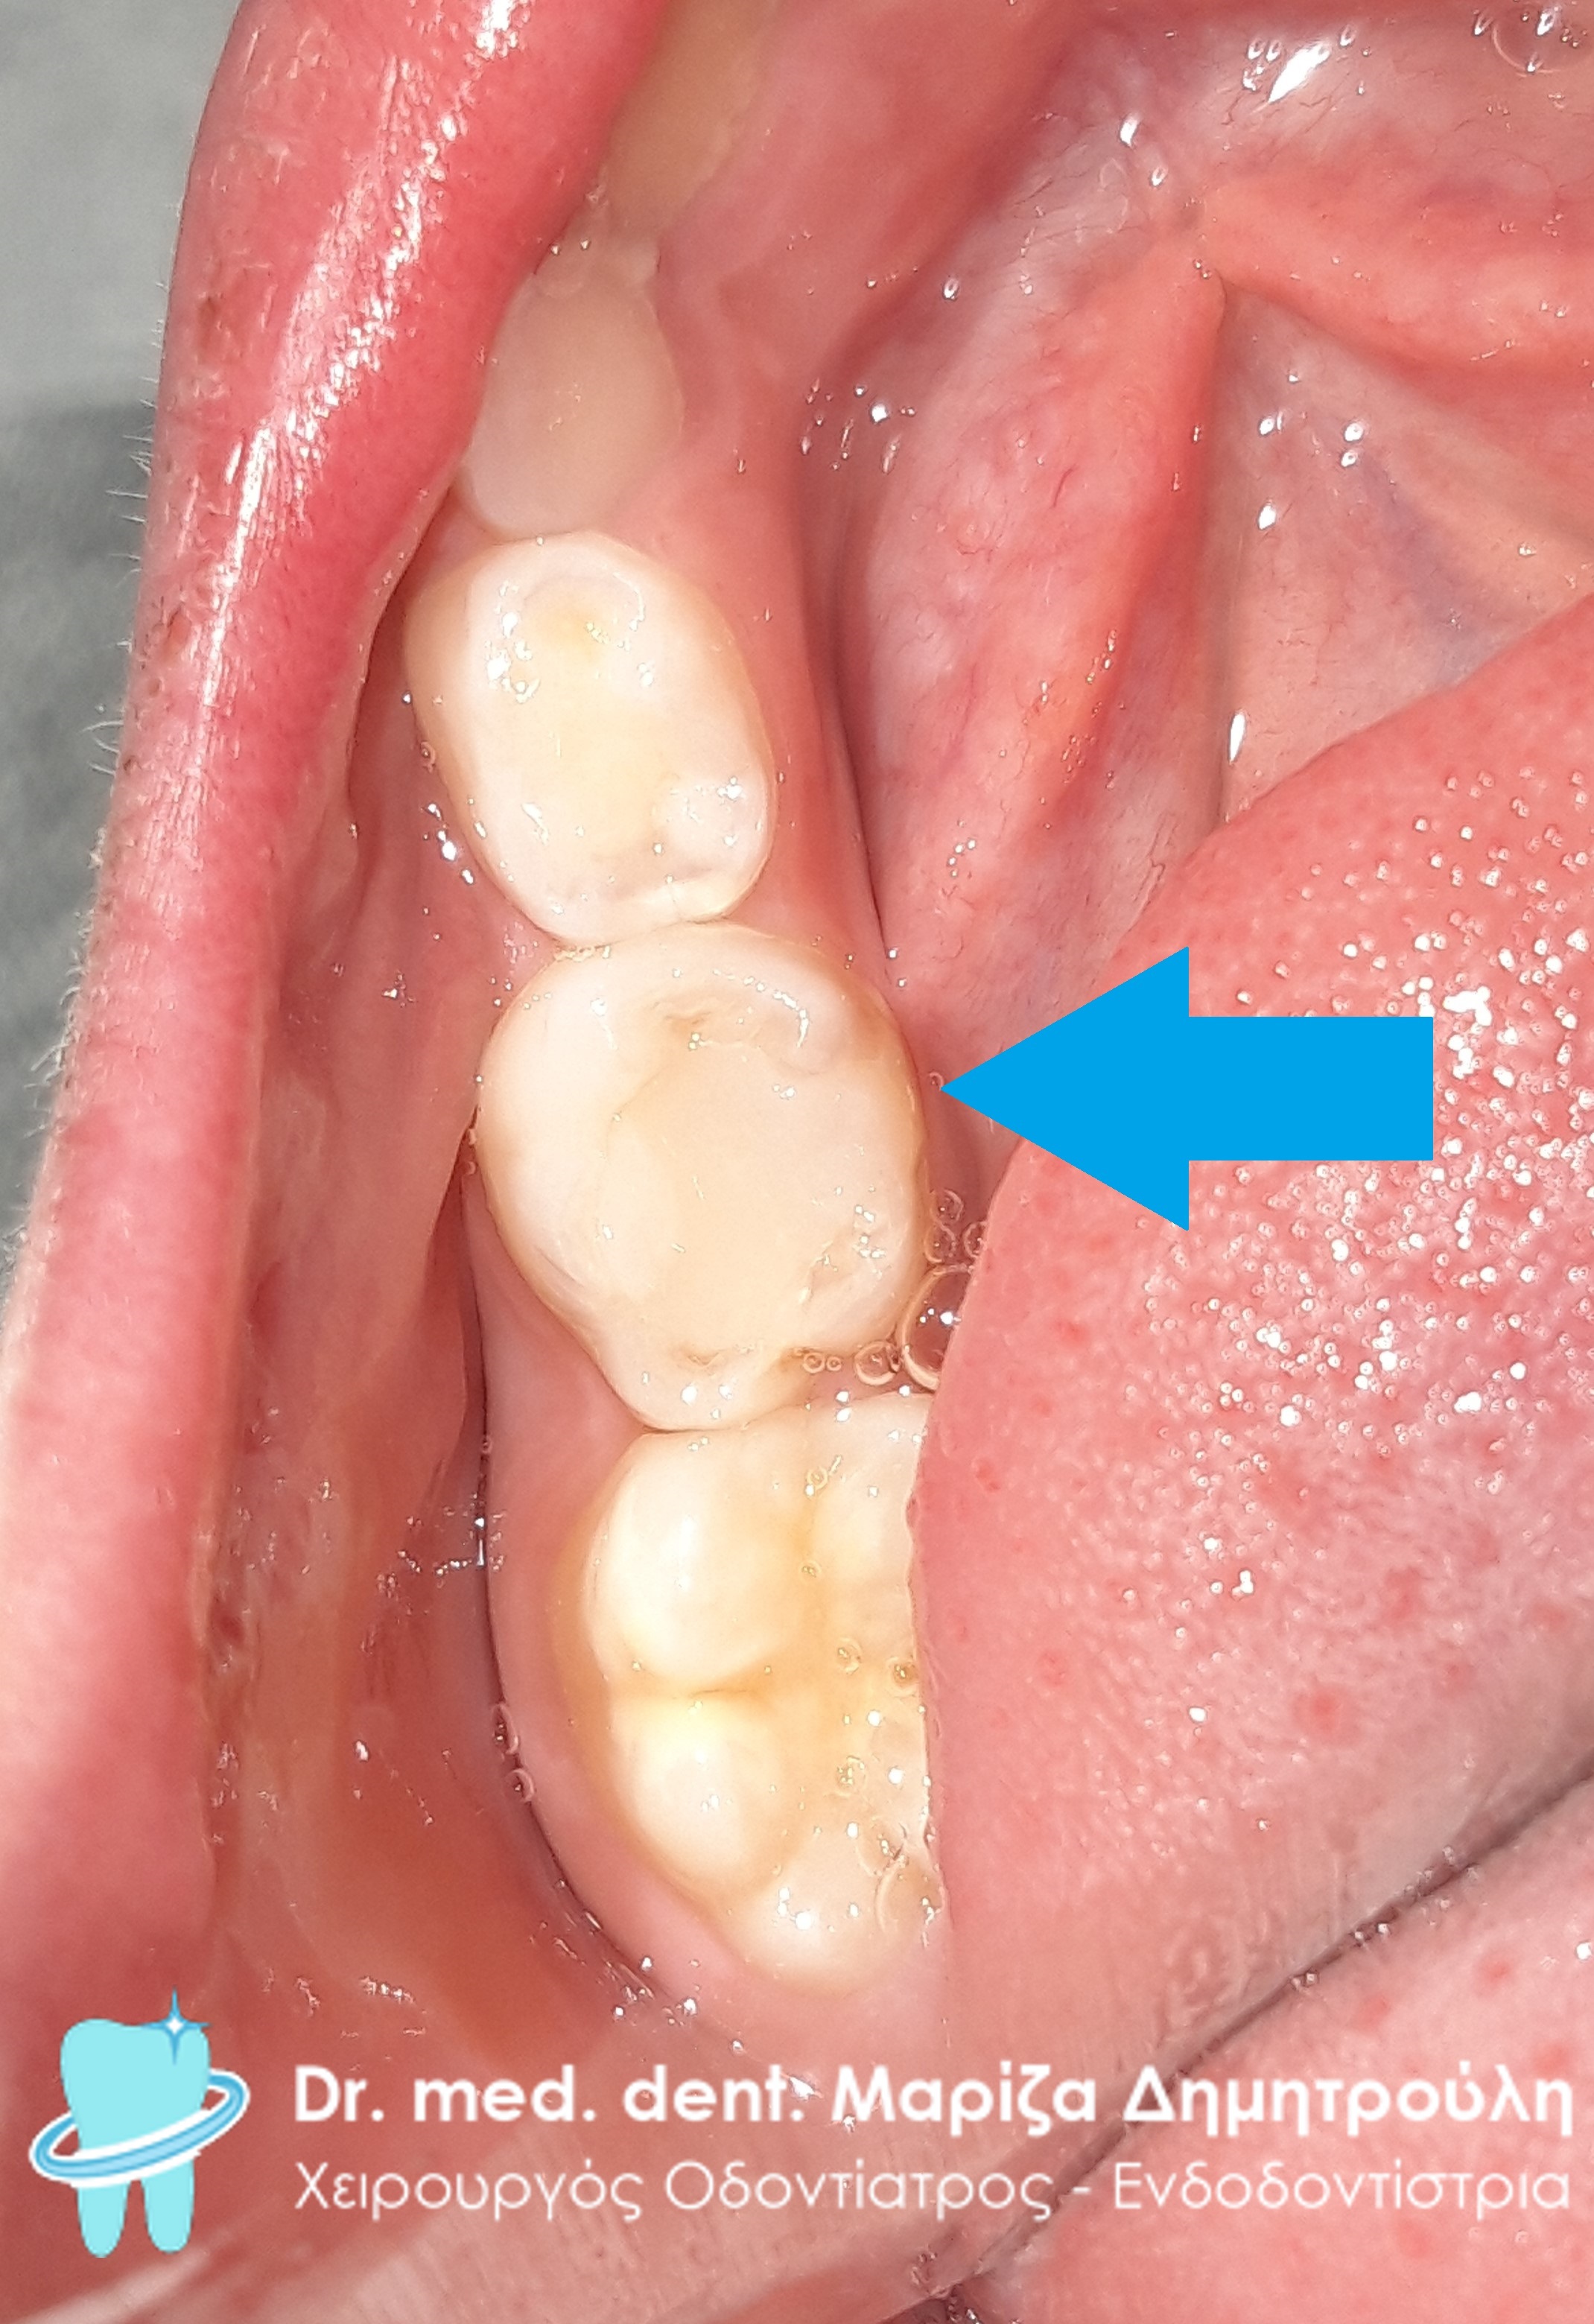

Αρχική κλινική εικόνα της αριστερής πλευράς της άνω γνάθου

Πλήρης αποκατάσταση της άνω αριστερής πλευράς με λευκά σφραγίσματα